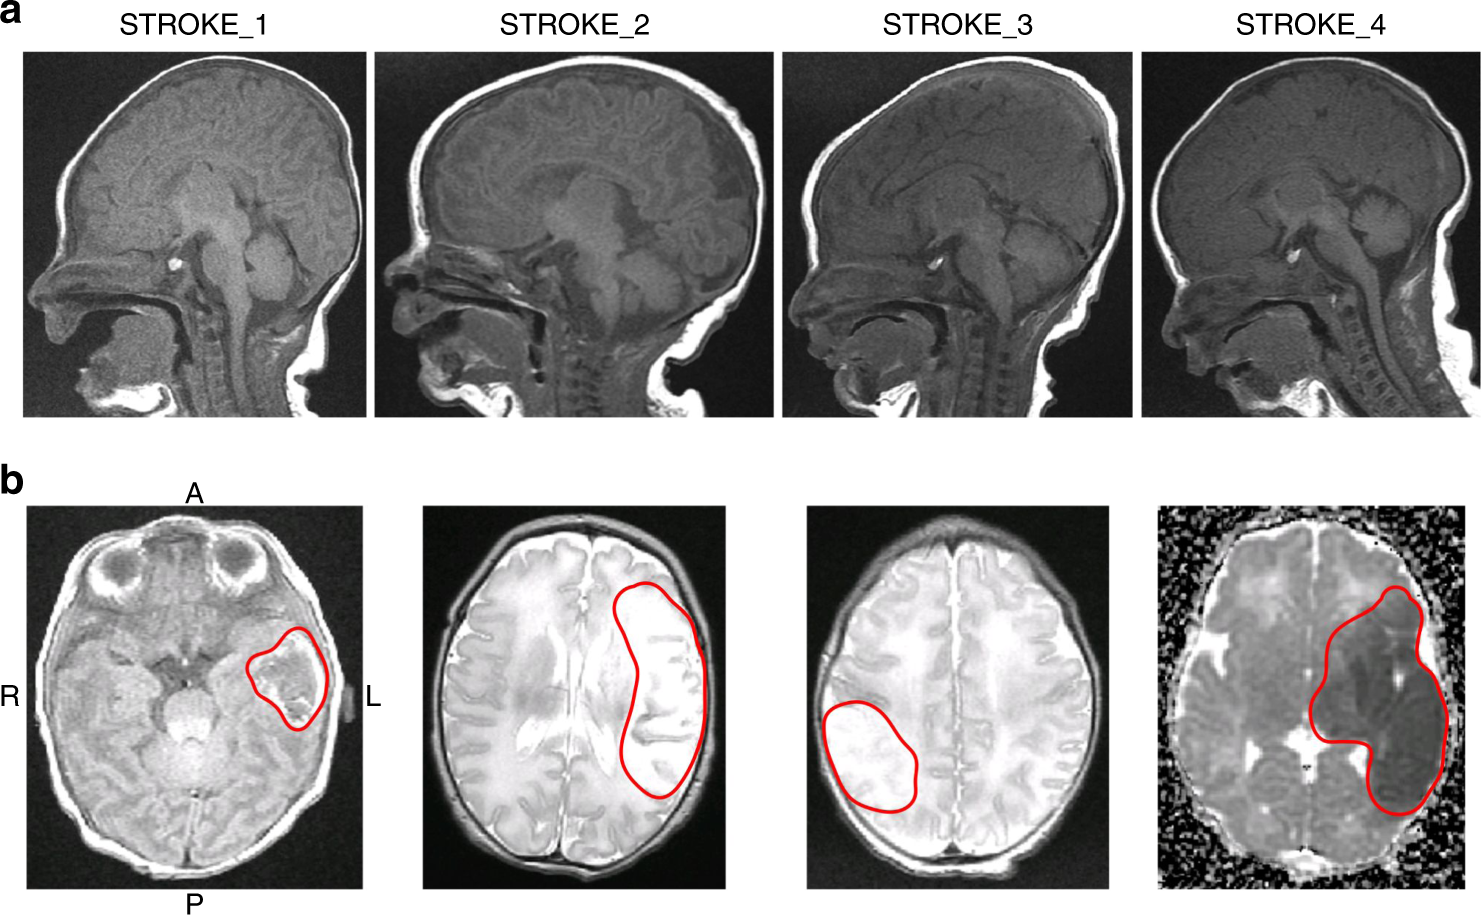

Fig. 2

Magnetic resonance images (MRIs). a Sagittal T1 spin echo (SE) views of each stroke-affected infant’s head, demonstrating the large variety in head shapes. b Axial slices showing abnormal signal in the stroke region (red line). A anterior, P posterior, R right, L left. The MRI sequence from left to right is T1-SE, T2 fast spin echo (FSE), T2-FSE, and apparent diffusion coefficient (ADC)